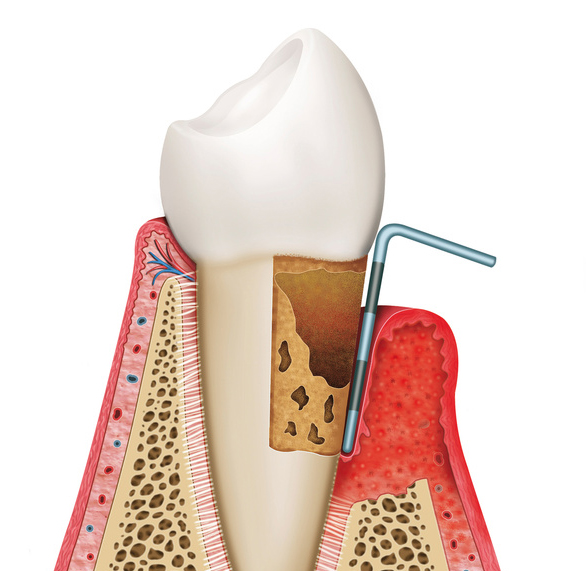

歯周病とは、歯の周りの組織(歯肉や歯槽骨など)が、プラークと呼ばれる細菌の塊内に存在する、歯周病菌に感染することによって引き起こされる、歯周組織の病気の総称を言います。

主な症状には、歯茎(歯肉)が腫れたり、出血したり、最悪な場合には歯自体が抜けてしまうこともあります。

歯周疾患の原因によって、歯肉が赤くなったり、腫れたりするなどの炎症が現れます。

歯肉炎となった後、歯肉炎が進行することにより歯と歯肉の付着レベルが破壊されてしまい、歯周炎となります。

歯周炎が重症化することで歯を支えている歯槽骨の吸収が進行し、その結果、歯の動揺が増大することで最終的には歯の喪失にいたります。

歯周ポケットの減少を目的として、切除療法、組織付着法(新付着術、フラップ手術)、再生治療法(歯周組織再生誘導法)などを行います。